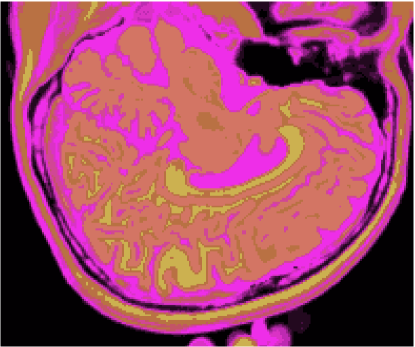

Os gráficos das figuras 14, 15, 16 e 17 mostram os resultados das medidas dos índices de fidelidade ϵMEsubscriptitalic-ϵME\epsilon_{\textnormal{ME}}, ϵMAEsubscriptitalic-ϵMAE\epsilon_{\textnormal{MAE}}, ϵRMSEsubscriptitalic-ϵRMSE\epsilon_{\textnormal{RMSE}} e ϵPSNRsubscriptitalic-ϵPSNR\epsilon_{\textnormal{PSNR}}, enquanto os gráficos das figuras 18 e 19 exibem os resultados do erro de quantização, Jesubscript𝐽𝑒J_{e}, e do índice de Omran, Josubscript𝐽𝑜J_{o}, para os métodos KO, CM, KM, IC-CAN, EQ-CAN, IC-PME e EQ-PME, em função dos níveis percentuais de ruído, para os 6 volumes de 181 fatias de 3 bandas. A figura 20 mostra os resultados de classificação, enquanto a figura 21 exibe os resultados de quantização para a imagem sem ruído da fatia 97, figura 5, usando os métodos IC-CAN-KM, IC-PME-KM, EQ-CAN-KM e EQ-PME-KM. É possível perceber a partir das imagens que a introdução da otimização dialética permitiu ao k-médias identificar diferentes classes dentro do fundo da imagem.

Refer to caption

(a)

(b)

(c)

(d)